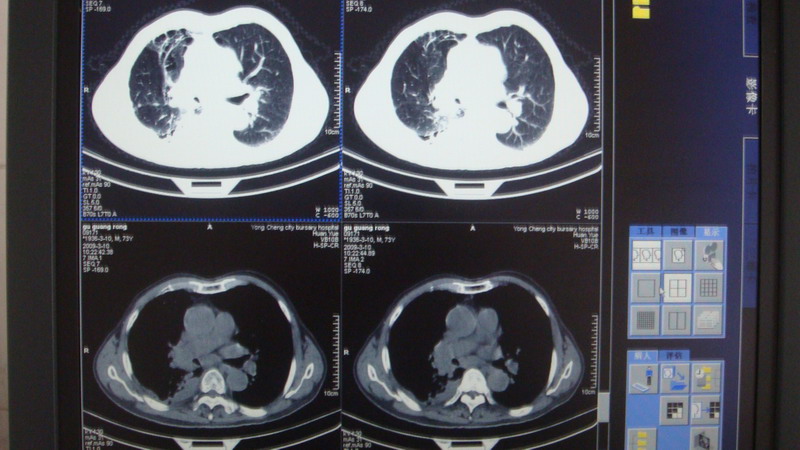

以下是引用光影相伴在2009-3-11 17:27:00的发言:[br]支持 右肺下叶周围型肺癌伴右肺门纵隔淋巴结转移;右上肺继发型肺结核(硬结\\纤维灶);右侧少量胸胸腔积液。另:不排除右侧胸膜转移可能。

以下是引用随光逐影在2009-3-11 16:57:00的发言:[br]支持 右肺下叶周围型肺癌伴右肺门纵隔淋巴结转移;右上肺继发型肺结核(硬结\\纤维灶);右侧少量胸胸腔积液。另:不排除右侧胸膜转移可能。

以下是引用草之原在2009-3-11 19:03:00的发言:[br]支持 右肺下叶周围型肺癌伴右肺门纵隔淋巴结转移;右上肺继发型肺结核(硬结\\纤维灶);右侧少量胸胸腔积液。另:不排除右侧胸膜转移可能。